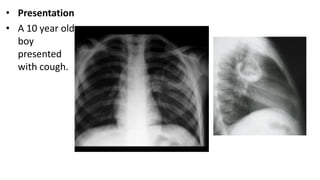

• Presentation

• Chronic cough

with right

hypochondrial

pain since

long time.

• A 10 year old

boy

presented

with cough.